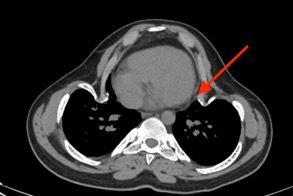

При исследовании состояния костной системы выявлено повышение маркеров костного ремоделирования: остеокальцин – 92,38 нг/мл (норма 24–70), С-концевой телопептид коллагена I типа – 1,39 нг/мл (норма 0,01–0,7). По результатам мультиспиральной компьютерной томографии грудного и поясничного отделов позвоночника отмечается выраженная кифосколиотическая деформация с прилежанием ребер к перикарду правого предсердия (Рис. 2).

Рис. 2. МСКТ грудного и поясничного отделов позвоночника.

Описание: выраженная кифосколиотическая деформация с прилежанием ребер к перикарду правого предсердия.